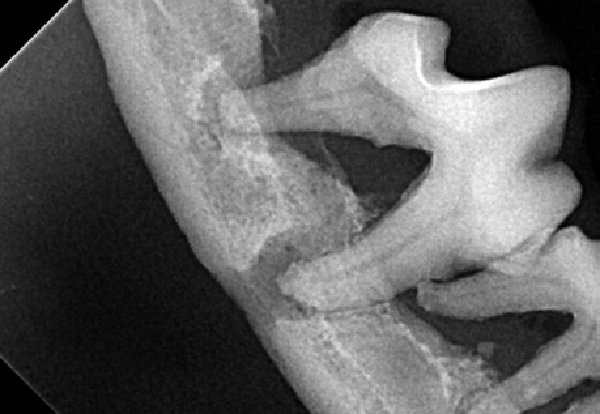

Figure 1B : Radiographie intra-orale de la première molaire mandibulaire droite d’un chien croisé de 5 kg souffrant de parodontite très avancée. Une infection endo-parodontale est notable avec lyse osseuse alvéolaire marquée, la mandibule est fragilisée.